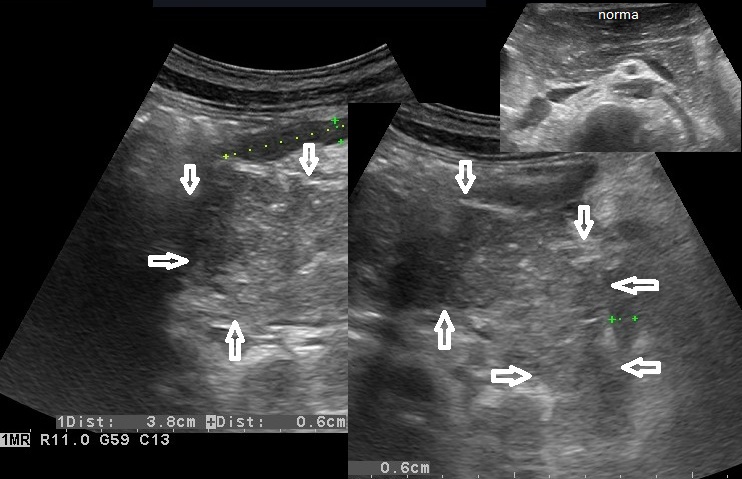

Rozpoznanie: W badaniu usg - trzustka pogrubiała, obrzęknięta (strzałki), przewód trzustkowy nieposzerzony (dla porównania na zdjęciu w górnym prawym rogu - prawidłowa trzustka u innego pacjenta). W badaniu TK (poniżej) - trzustka powiększona, niejednorodna, słabo odgraniczona od otoczenia, po podaniu kontrastu jedynie głowa fragmentarycznie na wysokości wyrostka haczykowatego ulega wzmocnieniu kontrastowemu, pozostały miąższ trzustki pozostaje hypodensyjny. Obraz ostrego martwiczego zapalenia trzustki.